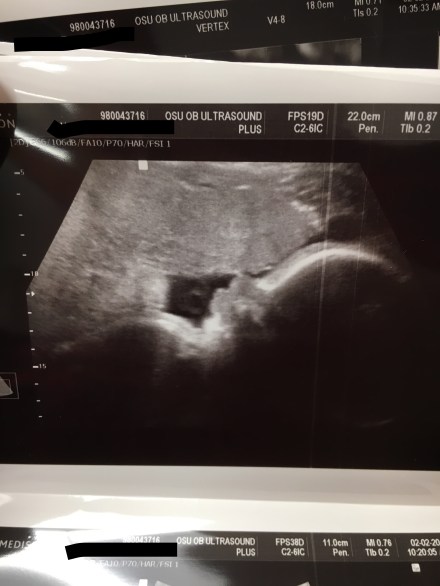

Now for some pictures.

A perfect little profile view (snuggled up to my anterior placenta- the white thing at the top of the pic)